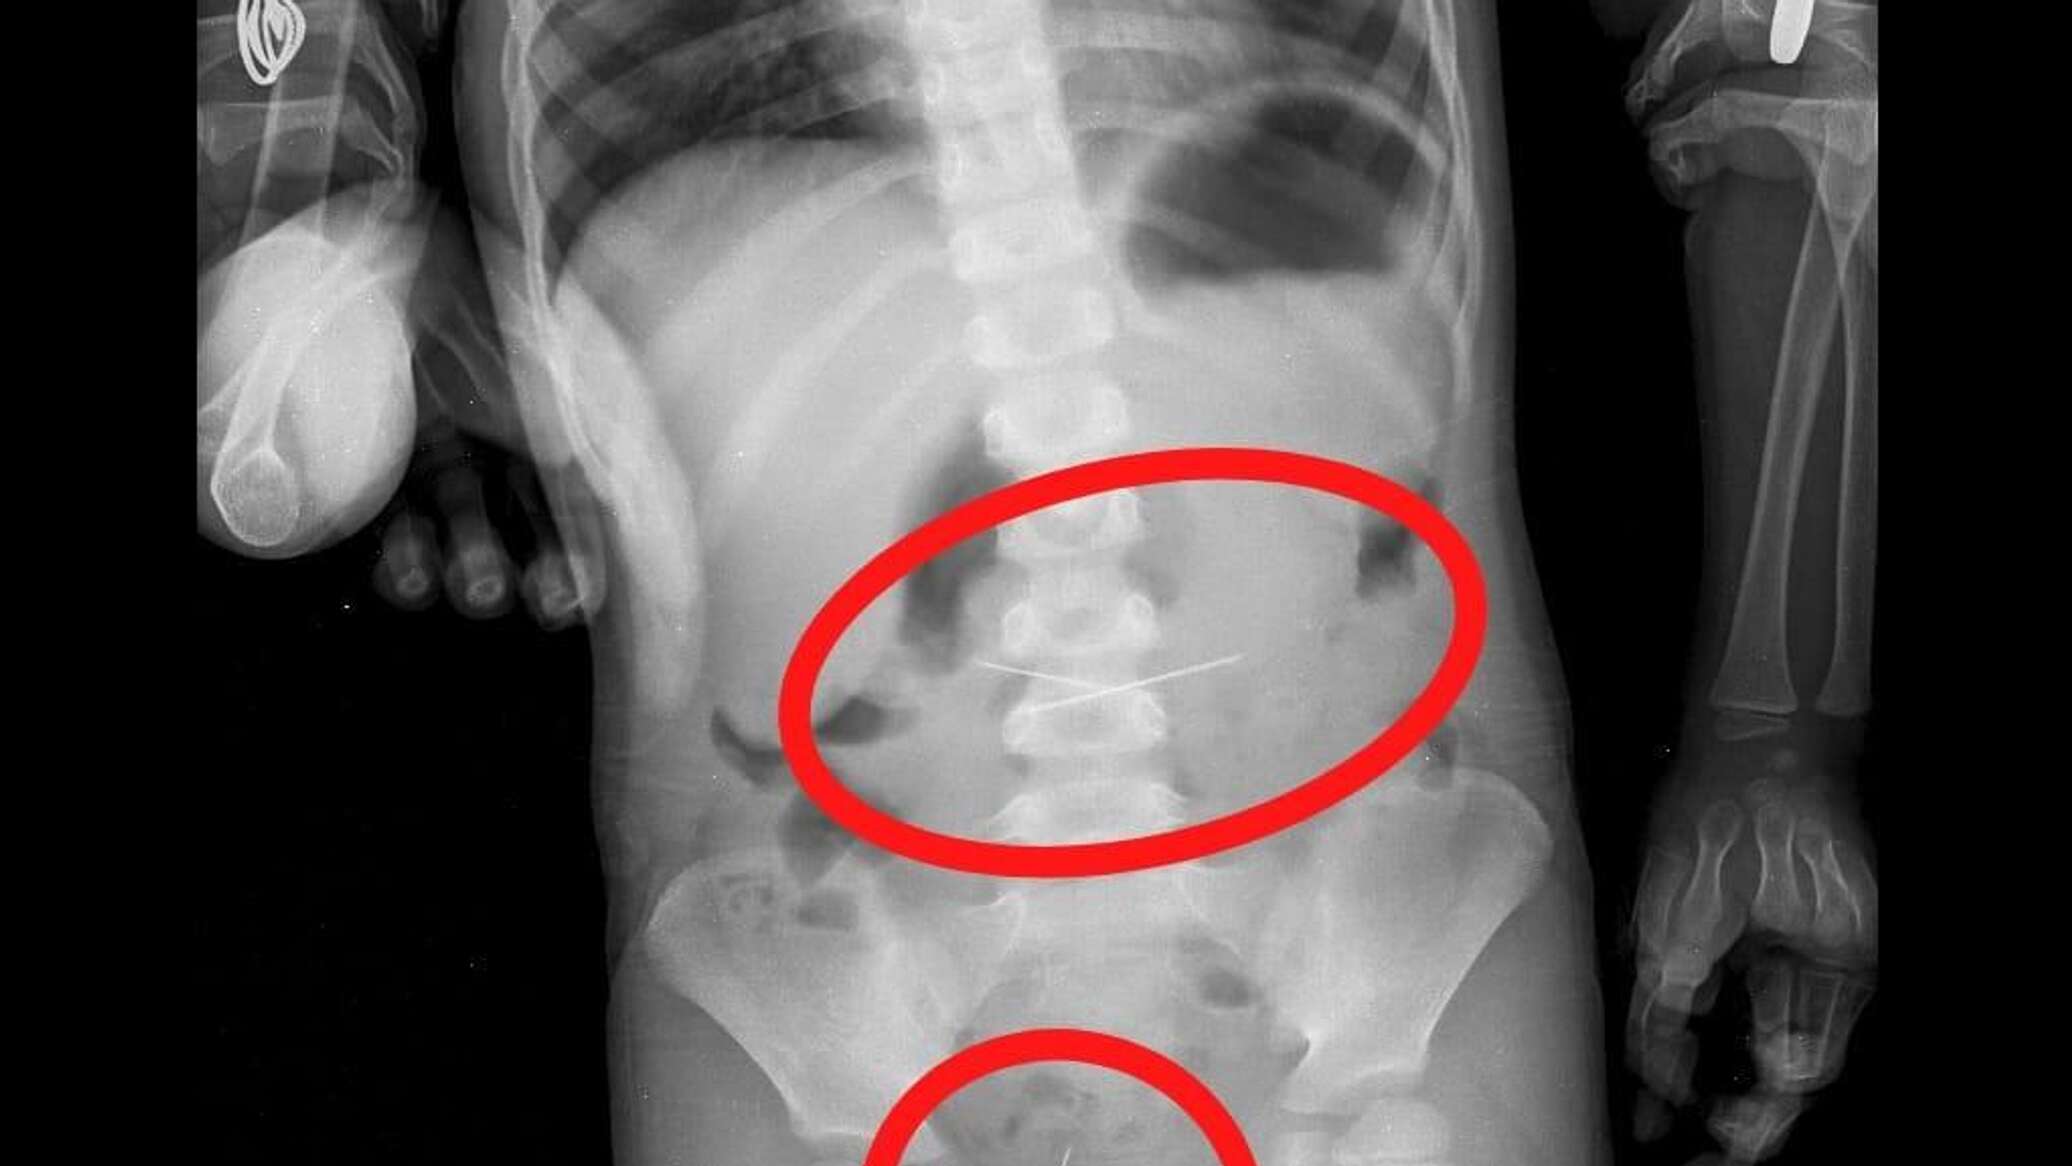

Ребенок съел книгу

Ребенок съел книгу 105 фотографий